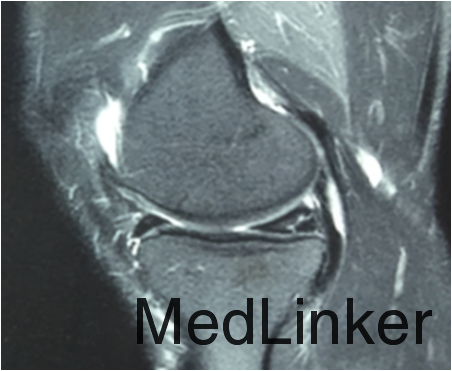

查体:左膝关节麦氏征(+),过屈试验(+),过屈位时内侧关节间隙触及囊肿。MRI检查提示:左膝内侧半月板损伤伴囊肿形成。

诊断:左膝内侧半月板损伤伴囊肿形成。行左膝关节镜检,内侧半月板周围囊肿切除+半月板修补术。术后开始行股四头肌肌力训练及踝泵训练,术后定期门诊复诊并行主被动康复训练。